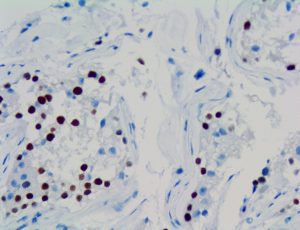

The first cytokines released are interleukin 1β (IL-1β) and tumor necrosis factor-α (TNF-α), which attract a variety of circulating white blood cells (WBCs) to the infection site, including neutrophils, monocytes, macrophages, and natural killer (NK) cells. This response, along with the antipathogenic chemicals released by these cells (i.e., complement), comprise the innate immune response. These cells directly attack the invading pathogen and also release additional cytokines, chief among them interleukin-1 and 6 (IL-6). IL-6 is essential for invoking the adaptive immune response, which calls T-cells, B-cells, and T helper (Th) cells to the infection site. IL-6 also stimulates further recruitment, proliferation and activation of macrophages.

It is the ICU physician who is most likely to witness one of the deadliest manifestations of the abnormal immunological response, the cytokine storm syndrome (CSS). This response is also referred to by some as the cytokine release syndrome (CRS). CSS is characterized by continuous activation and expansion of macrophage and lymphocyte populations, which secrete large amounts of cytokines, causing the cytokine storm. This massive cytokine release is akin to hemophagocytic lymphohistiocytosis (HLH) disease, a syndrome characterized by initial unchecked and persistent activation of cytotoxic T lymphocytes and NK cells.